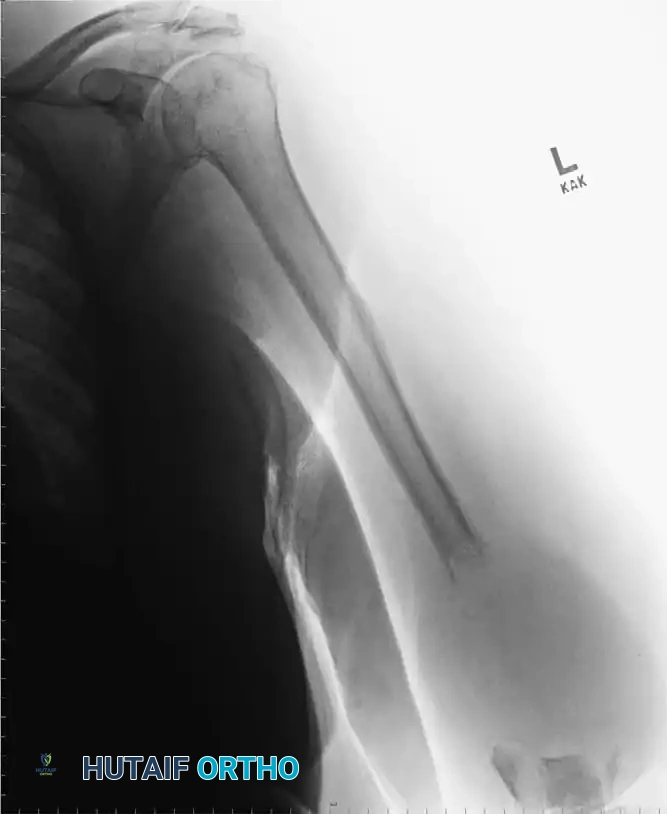

Image

Fig. 15-1 Anteroposterior (A) and lateral (B) radiographs demonstrating advanced bone destruction and periosteal reaction typical of subacute to chronic osteomyelitis.

While fewer than 5% of plain radiographs are abnormal at initial presentation, and fewer than 30% at 1 week, up to 90% will demonstrate abnormalities by 3 to 4 weeks. Arthrography can be utilized to document proper intra-articular needle placement during aspiration; however, contrast dye should only be injected after synovial fluid is obtained, as the bactericidal properties of iodinated contrast can yield false-negative cultures.